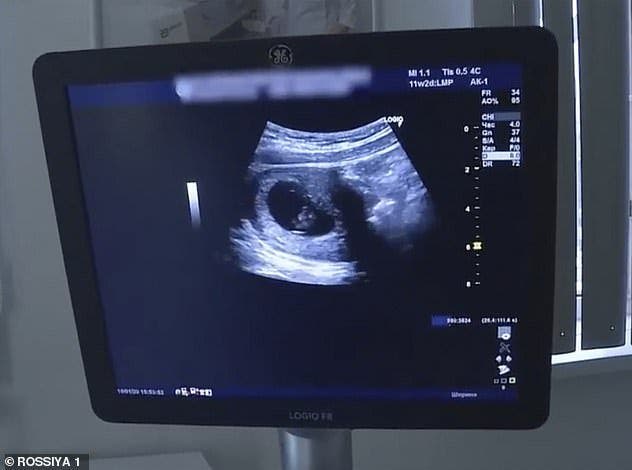

Une histoire insolite qui a secoué les médias concerne une affaire de grossesse entre des futurs parents encore « enfants » eux-mêmes. En effet, en Russie, et plus exactement dans la ville de Zheleznogorsk, Darya, une jeune écolière de 13 ans affirme être tombée enceinte d’Ivan, un garçon de 10 ans à peine, selon les médias locaux.

Face à cette nouvelle, la famille de la jeune fille s’est montrée solidaire et a assuré souhaiter soutenir sa décision de garder le bébé. Les deux enfants seraient même apparu à la télévision pour parler de cette grossesse.

Depuis l’annonce de cette grossesse assumée par les deux enfants impliqués, les médecins ont découvert via un test de paternité que le jeune garçon de 10 ans ne pouvait pas être le père de ce futur enfant, n’ayant pas encore franchi le cap de la puberté. Darya aurait ensuite révélé avoir menti pour dissimuler un viol dont elle a été victime.